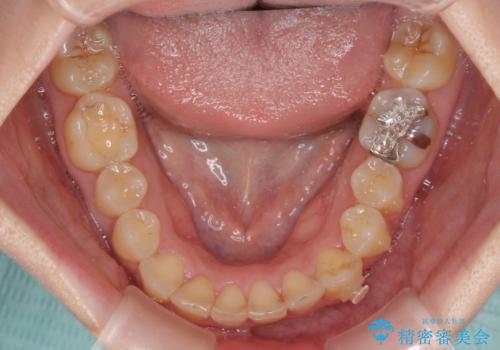

- 顕著な八重歯など、上下前歯のデコボコとスペースを気にして来院された患者様です。

八重歯改善には第一小臼歯の抜歯が必要であり、移動量が多いことから補助装置により八重歯を引き込むこととしました。

インビザラインでの治療をご希望であったので、インビザラインにて行うこととしましたが、右側前歯の改善にはワイヤー矯正が必要となる可能性があることをお伝えした上で治療を開始しました。

補助装置だけでなく、部分的にワイヤー矯正も使用しましたが、上下のスペースは改善しきれず、側切歯(前から2番目の歯)や顕著な八重歯は、インビザラインで治療するには限界があることがよく分かりました。

より良い仕上がりを希望される場合には、ワイヤー装置による矯正治療がお勧めとなります。